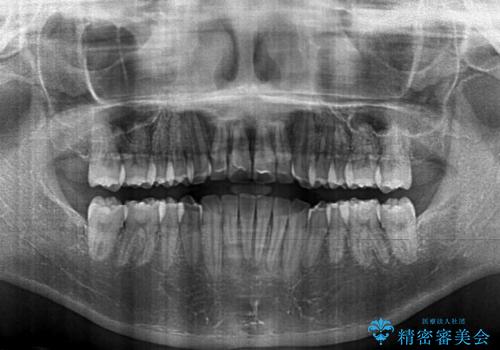

大きなトラブルもなく、順調に歯列が整ったため、僅か9ヶ月で装置を外すことができました。

あまりに短期間であったため、患者様自身も非常に驚いていらっしゃいました。